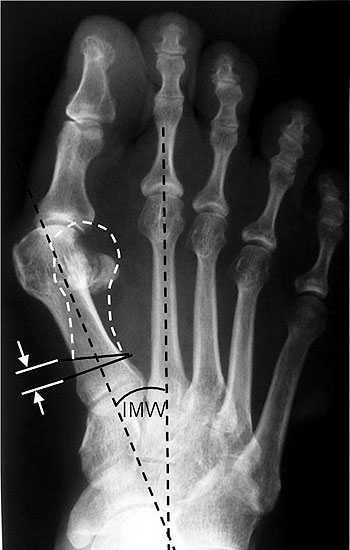

Präoperative Planung. Ziel ist es, den Metatarsalekopf auf den Sesambeinkomplex zu reponieren.

Abbildung 1

• Röntgenaufnahme des Fußes unter Belastung in d.p., schräg und seitlichem Strahlengang.

• Beurteilung des Intermetatarsalwinkels (IMA) und des distalen und proximalen Gelenkwinkels (DMAA, PMAA) (Abb. 1).

• Planung der Korrekturosteotomie: 1 mm Plattensteg korrigiert etwa 2° Intermetatarsalwinkel.